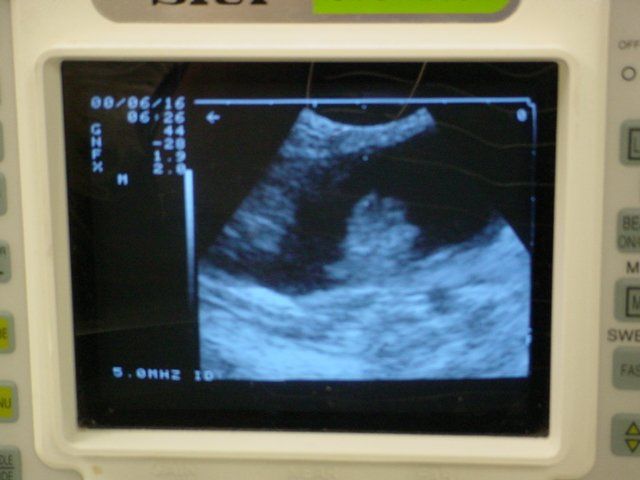

A dog was presented to All Pets for a second opinion. The dog had been experiencing bloody urine for several months. Antibiotics for infection failed to resolve the problem. An ultrasound revealed a large mass within the bladder. Urine is black on an ultrasound. The mass is the large white object in the center of the image at the left.